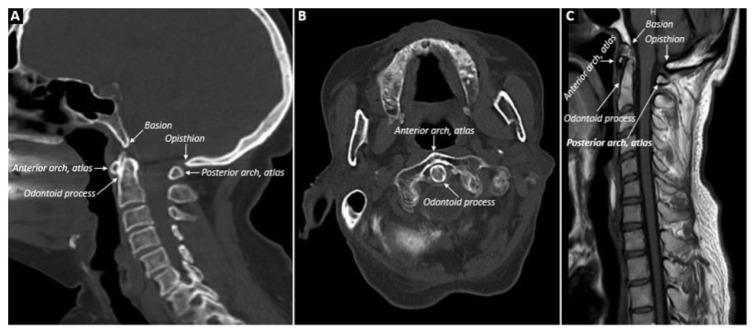

In this retrospective analysis, cervical CT or MRIs of patients with RA, SpA, or PsA, taken for any reason between 2010 and 2020, according to ICD-10 codes, were scanned. Demographic data of the patients were recorded. CCJ involvements (atlantoaxial, vertical, or subaxial subluxation, odontoid process involvement) were reevaluated by an experienced radiologist. The control group consisted of consecutive patients without inflammatory arthritis.

在这项回顾性分析中,根据 ICD-10 编码,扫描了 2010 年至 2020 年间因任何原因接受 RA、SpA 或 PsA 颈椎 CT 或 MRI 的患者。记录患者的人口统计学数据。由一位有经验的放射科医生重新评估 CCJ 受累(寰枢关节、垂直或下颈椎半脱位、齿状突受累)。对照组由连续无炎性关节炎的患者组成。